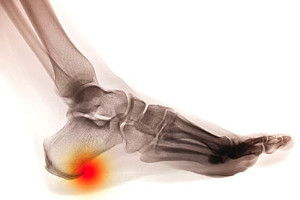

Obesity may cause pain in the majority of the foot. This is caused by extra weight the feet endure while daily activities are being performed. Many patients who are overweight notice they have heel pain, and this can lead to a condition this is known as plantar fasciitis. This is a result of a tear in the plantar fascia, which connects the heel to the toes. Relief is typically found if additional weight is lost, and when a mild exercise routine is frequently practiced. Many obese patients find it difficult to implement stretching and exercise techniques, and this is often because of the added weight that is carried around. If you are overweight and have foot pain, please speak with a podiatrist who can guide you toward implementing healthy lifestyle habits.

The more you weigh, the harder your feet must work to support your body. If you’re an obese individual and are concerned about your feet, contact Brent Harwood, DPM from Southeast Podiatry. Our doctor can provide the care you need to keep you pain-free and on your feet.

Obesity and Your Feet

People who are overweight are putting more pressure on their ankles, knees, and hips as well as their feet. This unfortunately can lead to variety of different issues.

Problems & Complications Stemming from Obesity

• When the body is overweight, it tries to compensate by changing the way that it moves. An obese person may lean forward and put extra weight on the wrong part of the foot. This puts unnecessary stress on the feet.

• Obese people are also more likely to develop type II diabetes which is a condition that causes a lot of foot problems. People with diabetes often don’t feel the cuts and sores that they may have on their feet, which can lead to more complicated and severe issues.

• Plantar fasciitis is another foot condition that can be caused by obesity. Plantar fasciitis is an inflammation of the tissue along the bottom of the foot, which causes pain and stiffness while walking and climbing stairs.